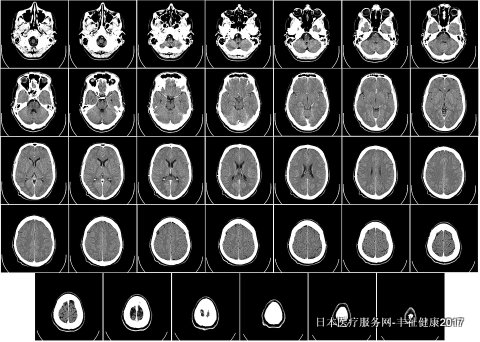

日本脑部精密体检,需要针对12对脑神经检查应按顺序进行,简单介绍如下。